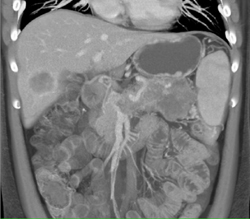

Diagnosis

Cystadenoma